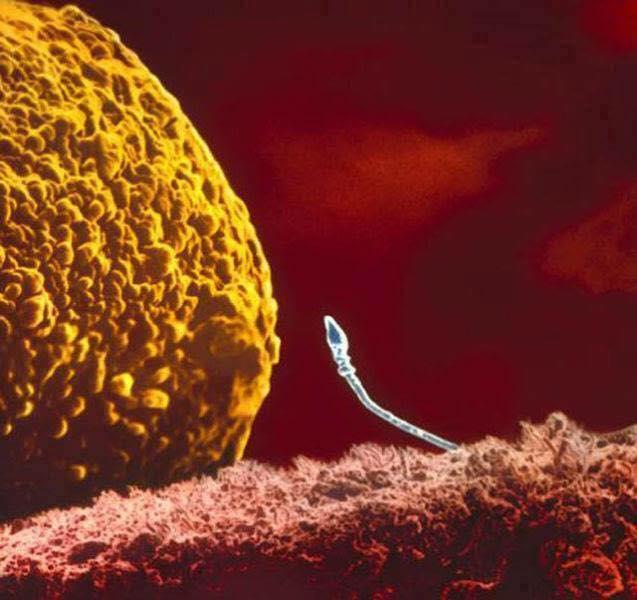

Chegada do espermatozoide no útero

Dois espermatozoides competindo pelo mesmo útero